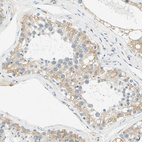

Immunohistochemical staining of human pancreas shows strong cytoplasmic positivity in exocrine glandular cells.